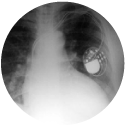

Valoración de marcapasos y cardiodesfibriladores